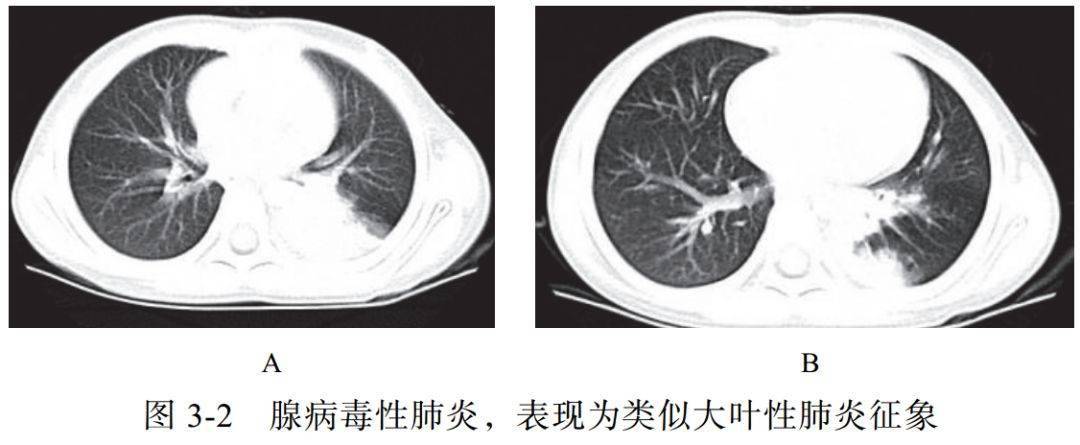

(二)腺病毒性肺炎

腺病毒属于哺乳动物腺病毒属,为无包膜的双链 DNA 病毒。腺病毒性肺炎易发生于婴幼儿或免疫功能障碍的人群。本病起病急,高热,并发症多

影像学表现:

(1)多呈大叶性分布(图 3-2A),实质、间质均受累

(2)可有空气潴留征、马赛克样灌注及肺气肿

(3)显示类似细菌性肺炎的支气管肺炎征象(肺叶或节段性分布),如腺泡结节、 GGO、实变等(图 3-2B)

(4)后遗症:闭塞性细支气管炎、支气管扩张、肺纤维化、单侧透明肺等